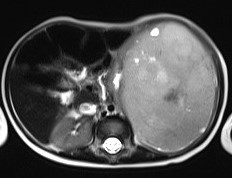

Img | CXR: LUQ soft tissue opacity MRI: high SI well-defined heterogeneous mass with central necrosis |

• MRI상 좌측 신장에 high signal intensity를 보이는 경계가 명확한 비균질종괴가 관찰되는데, 이는 윌름 종양을 시사하는 소견이다.